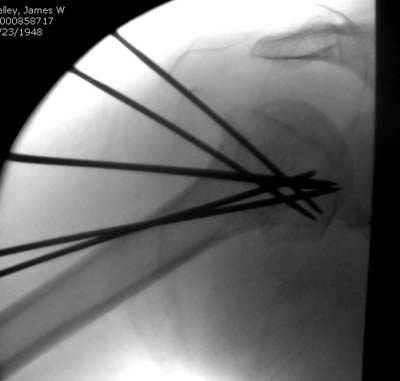

Здравствуй Женя. Во первых спицы, вводимые в головку плеча ретроградно, никогда не имели V-образную форму, если говорить о методике моей операции ЦИТО. Чтобы легче было запомнить Y-образную форму, вспомни крепление новогодних елочных шаров - очень демонстративно. Кроме того если ты внимательно посмотришь, то увидишь, что вся конструкция имеет некоторую кривизну по плокскости, величину, которой ты можешь задать сам. Сначала мы проводим проксимальный пучок, а в момент пересечения линии перелома мы

ротируем спицу таким образом, чтобы дистальный изгиб прямо противодействовал смещающим силам - поврот за ушко под контролем ЭОПа. Дистальный пучок стараемся провести так, чтобы его бранши расклинились и прошли по обе стороны предыдущего пучка, что создает дополнительное напряжение на

протяжении контакта. Для оценки правильности проведения спиц очень важно, чтобы ЭОП стоял строго перпендикулярно плоскости сустава, в противном случае - в рентгене есть эффект отбрасывания тени - прохождение косого луча дает удлиненное изображение спиыц и создается впечатление, что спица стоит уже в субхондральном слое. На первых операциях у нас было довольно частое несовпадение длины контрольной спицы и мы провизорно добавляли от 0,5 до 1,0 см уже на фиксирующем пучке. Входные отверстия лучше располагать по наружной и передней поверхности плеча на расстоянии не менее 2-х диаметров головки.

Такой выбор входных отверстий обусловлен прямой возможностью попадания в малый и большой бугорки за счет изгиба спиц по длине и отражения из от внутреннего кортикала проксимальнее точки введения. Поскольку анатомически бугорки не составляют артикулирующую поверхность, то некоторое выстояние спиц только усилит стабильность. Входное отверстие мы используем 6 мм в диаметре, для эффективного раскрытия петли-пружины. Спицы перед проведением

проверяем на достаточную эластичность и упругоустойчивость, мягкие спицы отбраковываем. В данном примере создалось впечатление, что одна бранша V-спицы скользнула по картикалу снаружи? Все это безболезненно можно переделать, расширив теже отверстия, изогнув спицы, повернув их в разные стороны и добавив еще пучки Y-ОБРАЗНЫХ, а не V-образных (эти пучки выталкивает, особенно если они прямые - пружина работает в обе стороны).

Посылаю послеоперационные Рг граммы.

Поздравляю, получилось просто замечательно. Если можно, расскажи чуть подробнее, как делали - как вправляли, как вводили спицы, поворачивали ли их?

Я и сам доволен результатом. В предпоследнем письме я кратко описал ход операции - закрыто репонировать не удалось( 2 недели с момента травмы и 1 неделя после неудачной репозиции) после удаления пучков спиц, пришлось сделать - 2см разрез на уровне перелома и с помощью периостального элеватора (золотое правило механики) *одеть* головку на дистальный отломок.

Спицы проводил через старые отверстия, вращая пучок импактором- направителем при его введении в головку.